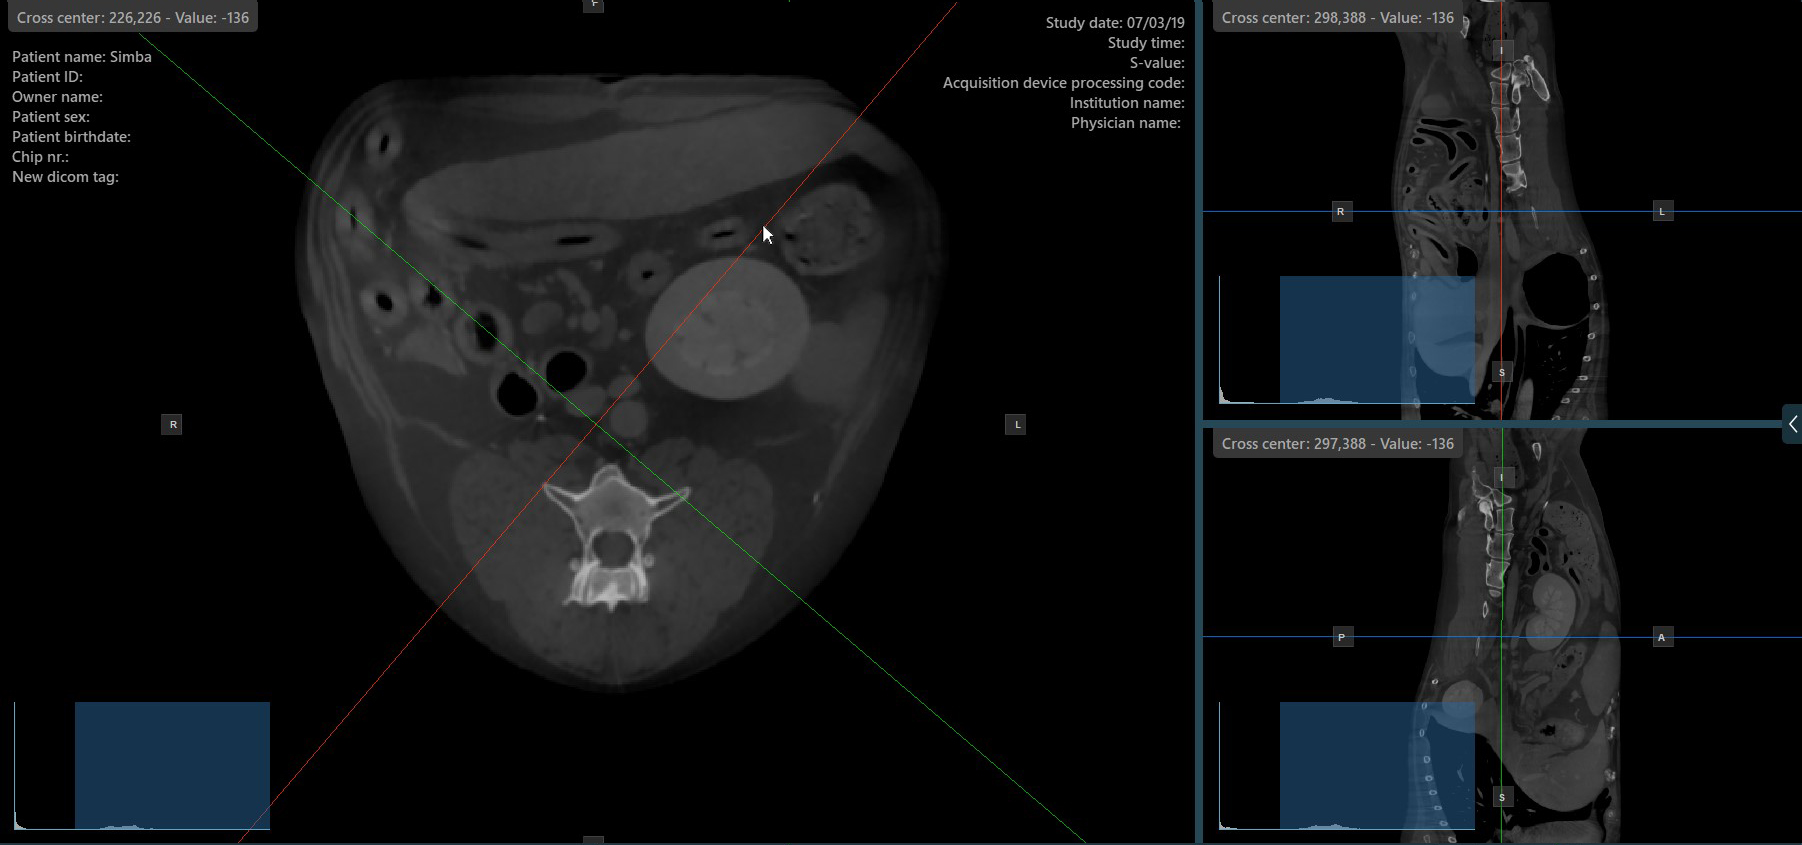

Alapértelmezés szerint minden szeletelő külön forgatható. A CT-nézegető bal oldali eszköztárában a megfelelő ikon kijelölése deaktiválódik, amikor a szeletelők egyenként vannak forgatva.

A szeletelők egyidejű forgatásának aktiválásához nyomja meg a bal oldali eszköztár Merőleges szeletelők ikonját. Függetlenül az előző orientációjuktól, a szeletelők úgy kerülnek áthelyezésre, hogy merőlegesek legyenek egymásra.

A szeletelők aktív módjának váltásához kapcsolja be vagy ki a Merőleges szeletelők opciót bármikor, vagy válassza a CT-megjelenítő menüjéből a Eszközök -> Merőleges szeletelők vagy a Eszközök -> Külön szeletelők opciók egyikét.